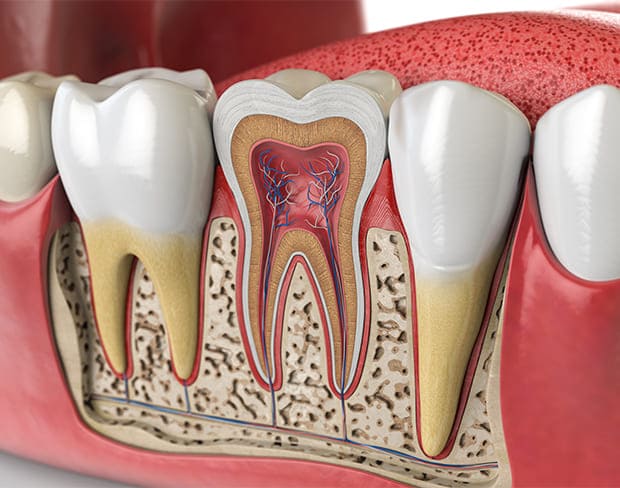

根管治療とは一般的には歯の根(根管)についての治療の事を指します。歯の中には歯髄(神経)という軟らかい組織があり、根管の先のほうの小さな細い孔(あな)で、顎骨の中の神経や血管とつながっています。

この歯髄が悪化した虫歯や外傷で、細菌の感染を受けたような場合には、歯がひどく痛んだり、歯肉が腫れたりします。

このような症状を改善させるには歯髄を除去して歯を残す治療をしなければなりません。